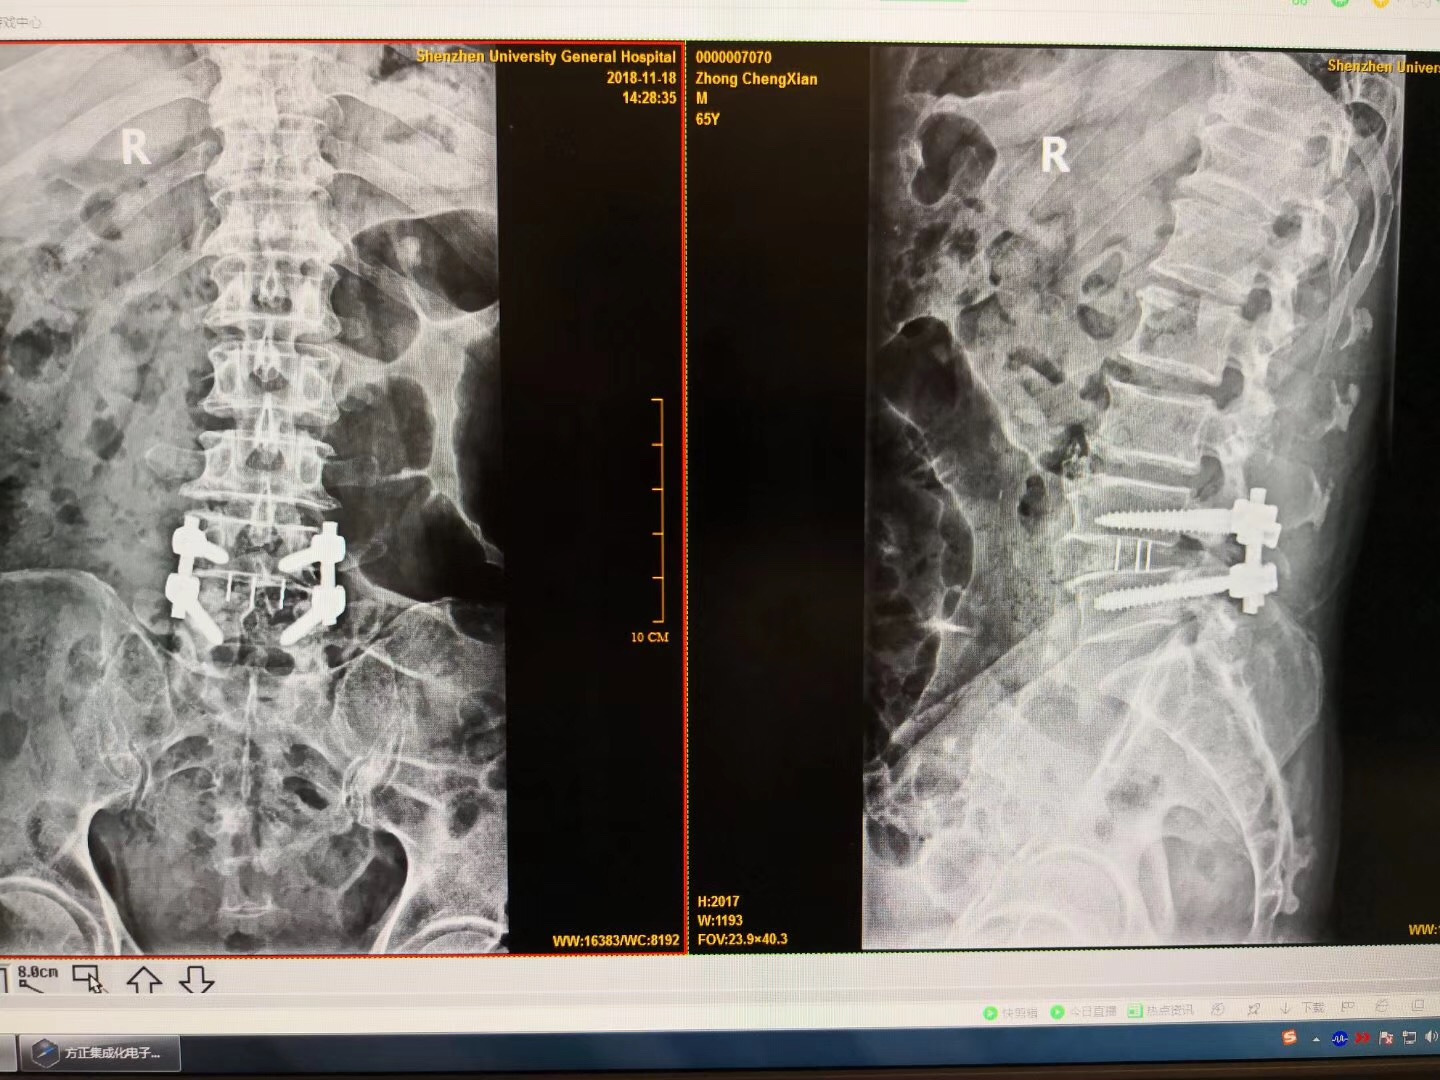

诊断:腰椎间盘突出伴椎管狭窄症(L4/5节段),腰椎不稳定(L4/5节段),予施行“后路腰椎管减压固定融合术”治疗。

术后:术后第二天患者即可腰围保护下床行走活动,双下肢麻痛基本缓解,效果良好!